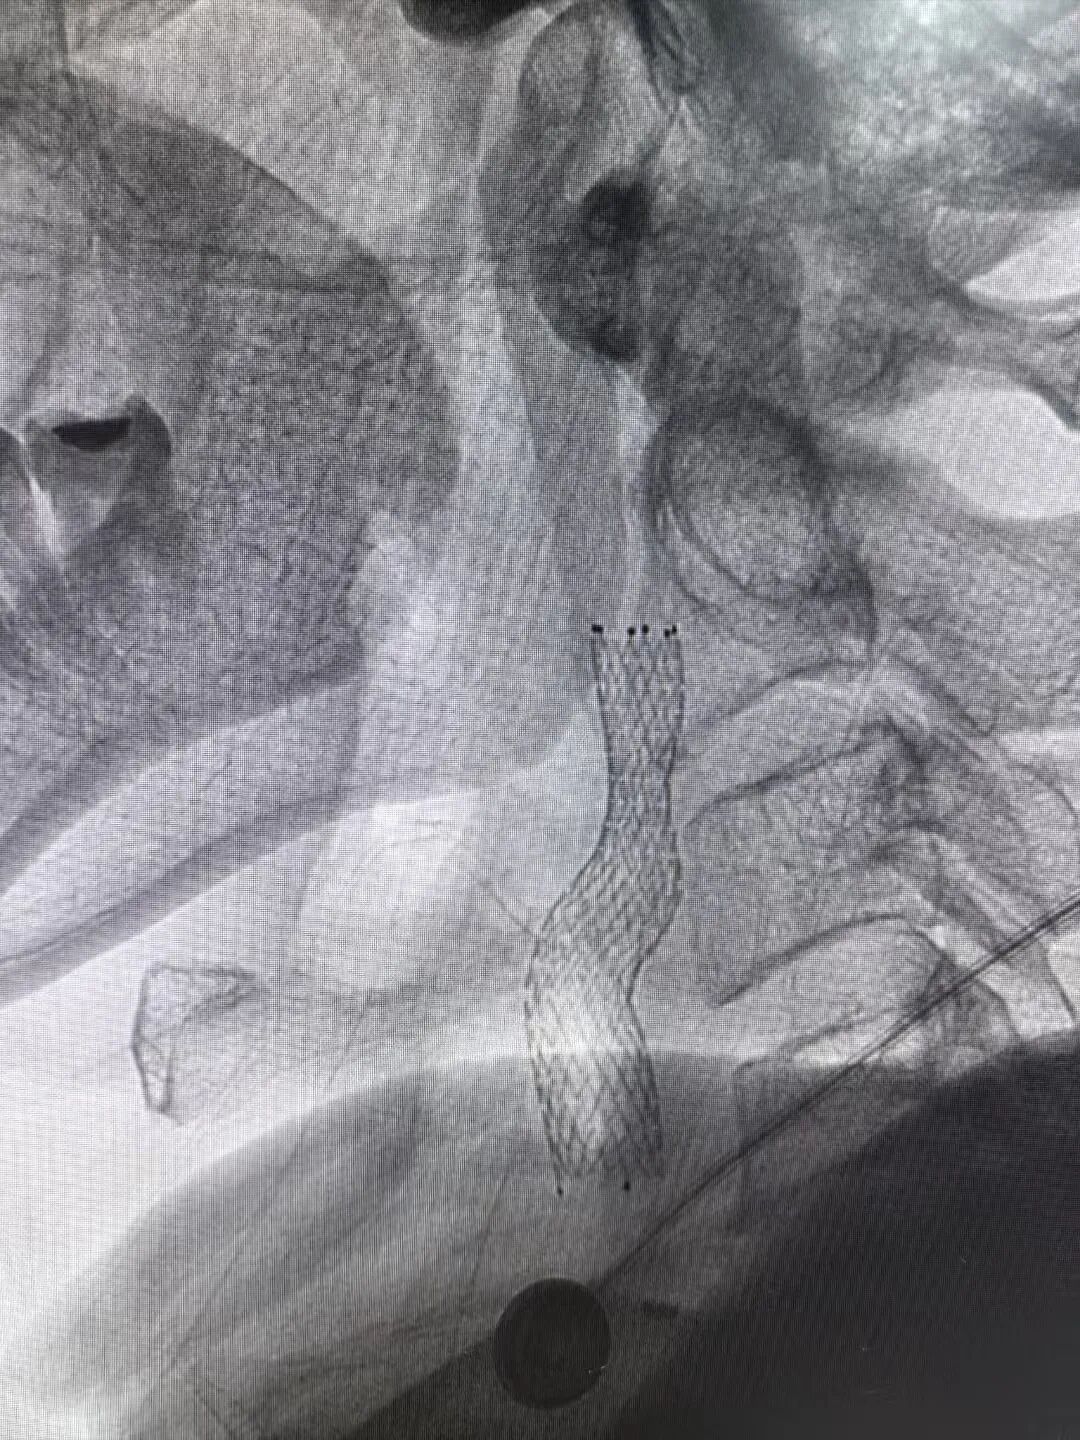

冠脉造影显示患者前降支血管重度狭窄

2025年3月4日手术当天,医生穿刺患者右桡动脉进行造影时,一场危象毫无征兆地出现:患者前降支血管近段狭窄达99%,血管近乎完全闭塞。这意味着心脏随时面临因严重缺血而停跳的危险,大脑也承受着巨大且不可逆的缺血性损伤风险,情况刻不容缓,必须立即进行紧急手术,这是挽救患者生命的关键。

在征得家属同意后,医疗团队优先为罗先生实施心血管手术。然而,就在准备植入支架的紧要关头,患者突发室颤导致心跳骤停。经验丰富的手术团队临危不乱,立即启动应急预案,果断实施胸外按压,并给予两次精准电击除颤。在惊心动魄的几分钟后,罗先生的心脏终于恢复搏动。稳住患者生命体征后,玉溪市中山医院心内科业务主任李驹凭借精湛的医术,精准、迅速地将支架植入堵塞血管。随着支架成功撑开,停滞的血流瞬间恢复通畅,罗先生的心脏危机暂时得以化解。